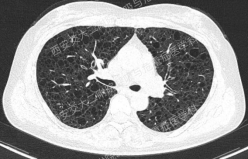

上图所示肺部多发囊性病变,双肺广泛分布,直径在2-10mm之间,壁薄,囊壁间组织相对正常。结合育龄期女性等临床资料,不难诊断淋巴管平滑肌瘤病(LAM)。对疑似LAM的女性的初步评估还应包括血管平滑肌脂肪瘤的筛查、淋巴管受累以及是否存在未被诊断的结节性硬化症。该例患者经评估后诊断散发型S-LAM。